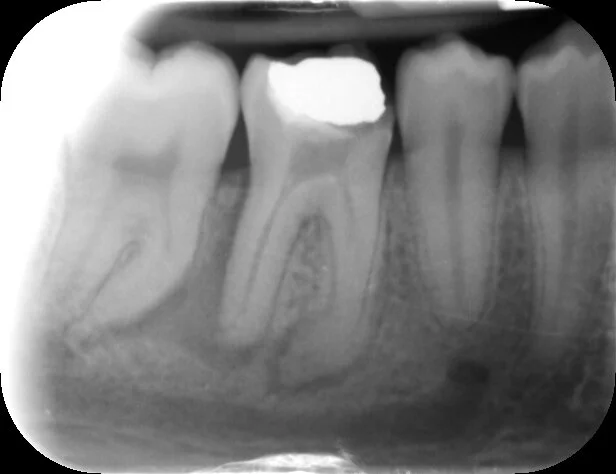

Post-op PA shows all canals well prepared to the apex